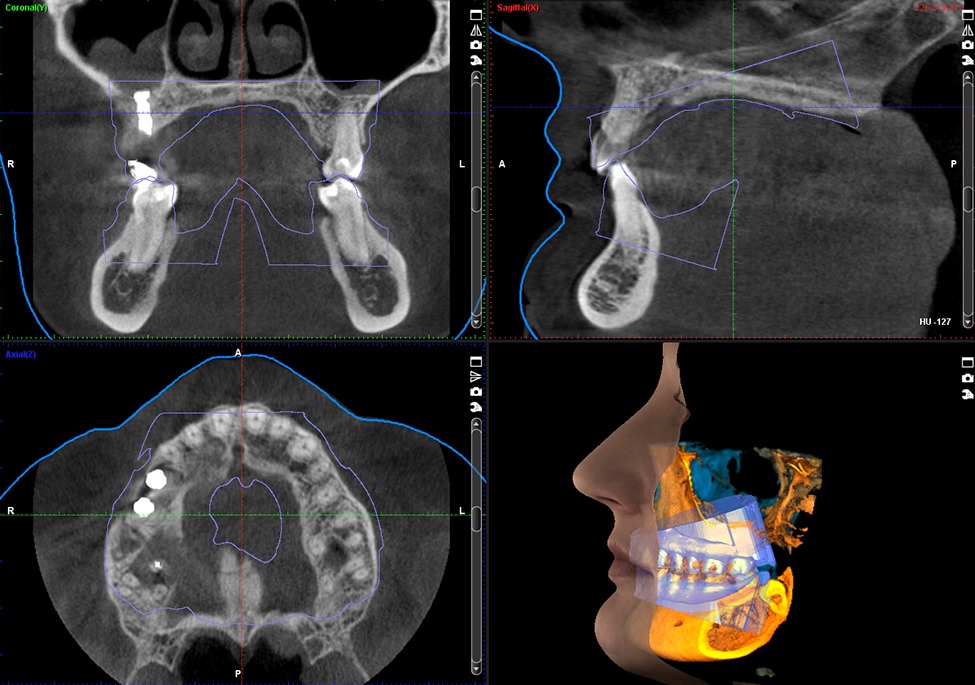

- Practical training sessions and hands-on case interpretations of volumes on CBCT software.

- Introduction to the software followed by Hands-On.

- CBCT in Orthodontics, Impacted teeth and malocclusions

- Image guided implant planning and assessment

- Digital Implant planning using digital impressions and CBCT scan on advanced implant planning software.